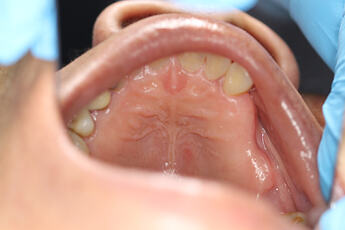

after 2 months of healing:

i plan to keep the 2mm of connective tissue on the buccal flap , because the bio guide membrane needs to stay on the hard sound bone rather than defect of previous extraction site (with less sound bone), not sure if you guys agree with the flap design, the proximal gingival papillae was preserved as there is some recession on UR7 , which would make suture difficult.

after degranulation bur and curettage of the socket, despite we had done similar things 2 months ago after XLA. there was oral astral communication with per formation of sinus membrane. the defect of the OAC is around 1-2mm, but the crestal defect is 4.5mm by 7mm wide as measured.

( I designed the bio guide dimension, not sure if 4.5mm by 7mm would be able to cover the OAC defect, which is much smaller at the base of the UR6 socket)